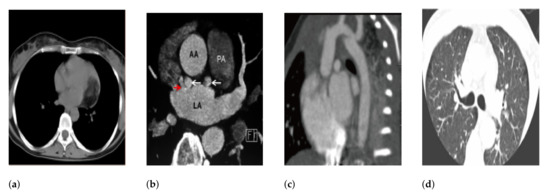

- We discuss the problem of intra-class and inter-class variability in medical image classification.